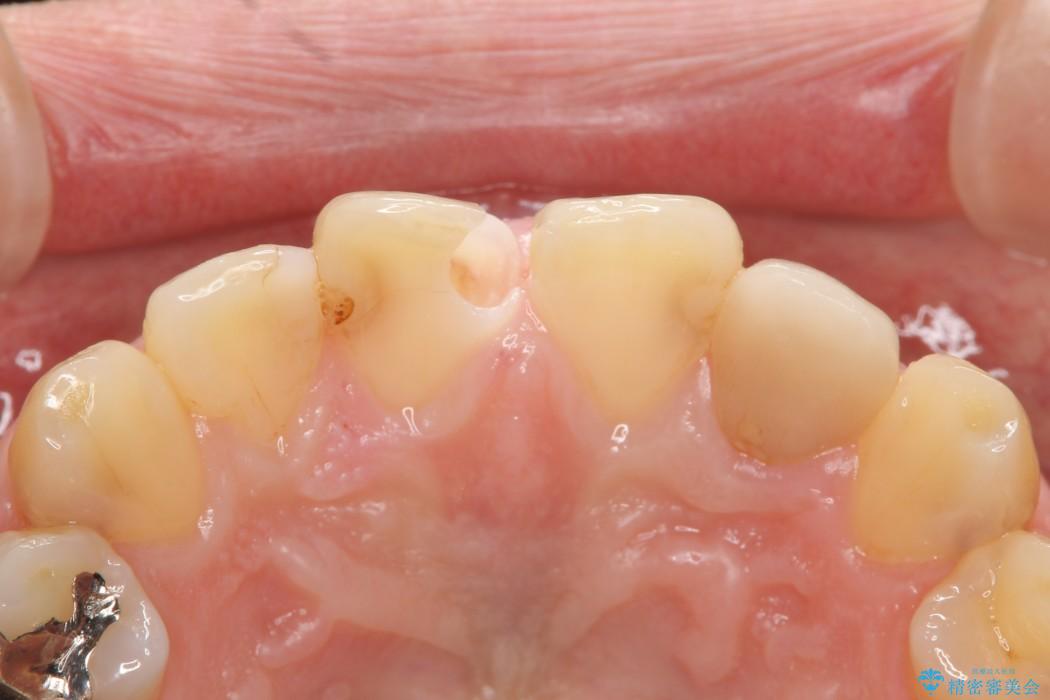

虫歯による歯の欠けと変色を主訴に来院されました。

神経に届く一歩手前の虫歯を前歯に認めました。

虫歯の範囲が大きいため詰め物ではなく、被せ物を使用した治療を行うこととしました。